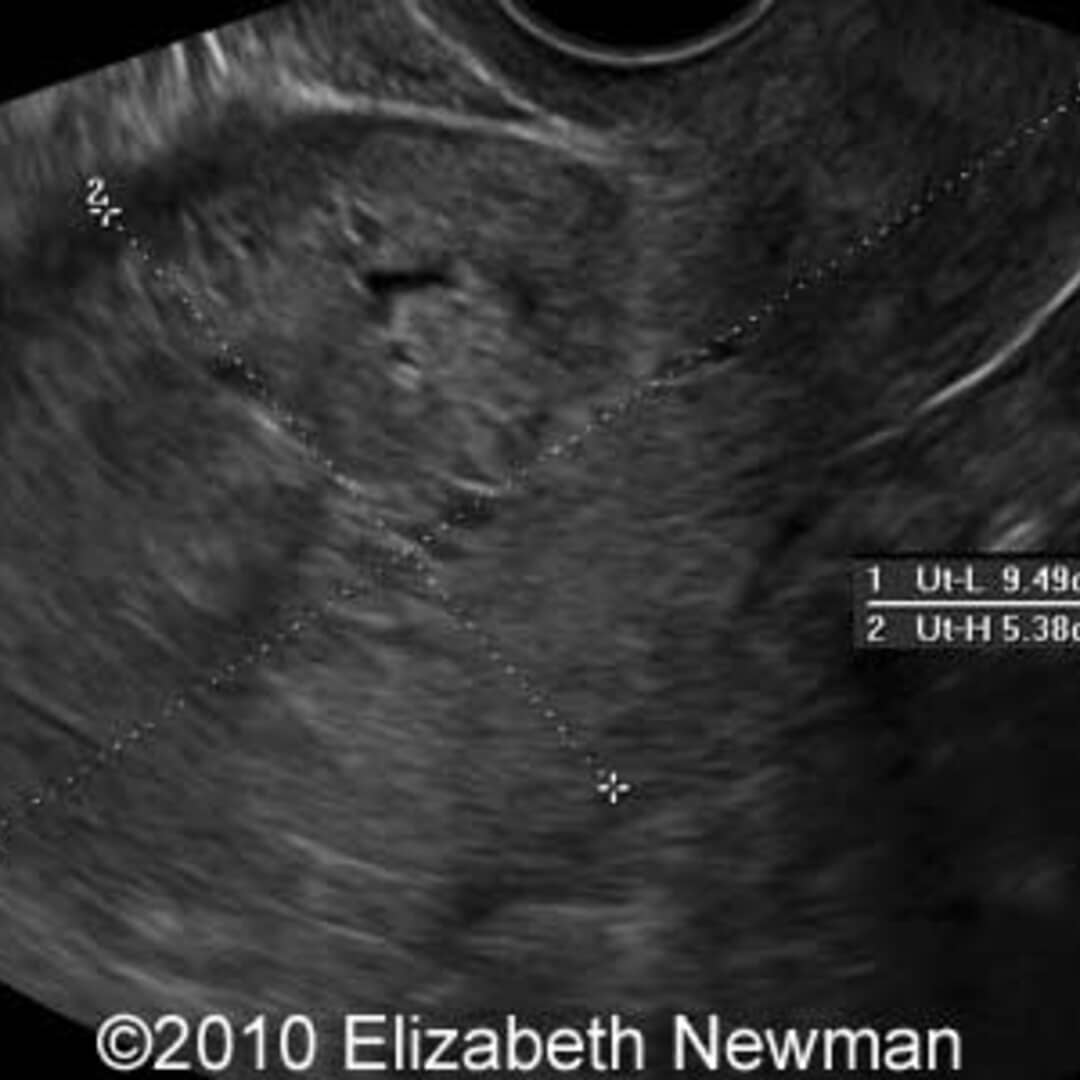

pregnancy molar ultrasound complete trimester first goo twin glowm fig diagnostic placenta normal resources

Molar Pregnancy | Point-of-Care Ultrasound Certification Academy

Molar Pregnancy | Point-of-Care Ultrasound Certification Academy www.pocus.org

Case Study: Molar Pregnancy | Case Studies | POCUS.org

Case Study: Molar Pregnancy | Case Studies | POCUS.org www.pocus.org